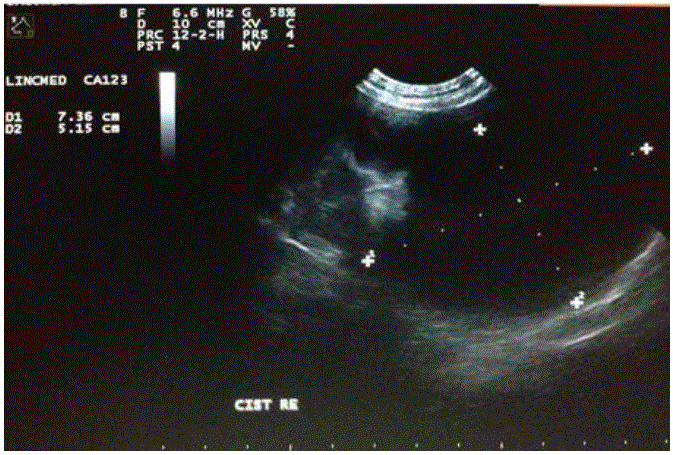

血象、血清生化和尿液分析均未发现任何变化。随后,患者接受腹部超声检查,结果显示左侧肾皮质存在囊性结构,大小为7.3cm×5.1cm(图2),右侧肾皮质大小为1.0cm×1.0cm。胸部X光片未显示与转移瘤相符的图像。

图2:超声影像显示一个囊肿在左肾皮质一个7岁的混血母狗。